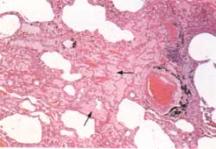

5.病理改變原發性肺炎克雷白桿菌肺炎多以大葉分布,常見於肺上葉,尤其是右上葉;繼發性肺炎多以小葉分布,為雙肺斑片樣支氣管肺炎樣表現,多肺葉、雙側性及小葉分布者少見,總體病理與肺炎球菌肺炎相似,但發展較快,無明顯肺炎的階段性變化,但有其自身特點:①屍檢病變肺葉,其切面可見到黏液樣滲出物流出,或可以挑起黏稠的絲狀滲出物,這是其病理的特徵性改變。②肺組織破壞迅速,4天之內可形成多發性膿腫或單一大膿腫,肺泡壁破壞,致肺泡萎縮,肺容積減小,主要肺血管可發生栓塞,引起繼發性肺壞疽、壞死。③常合併胸膜侵犯,發生胸膜纖維素性滲出,粘連,其發生率約為25%,甚至合併心包積液。④早期組織學檢查中,可見到水腫液、單核細胞及細菌,後期可見肺泡壁破壞,有大量多形核中性粒細胞,纖維組織增生活躍,易發生機化改變。⑤可致肺內出血、膿氣胸、心包炎、支氣管擴張等改變,部分可成為慢性克雷白桿菌肺炎變化。